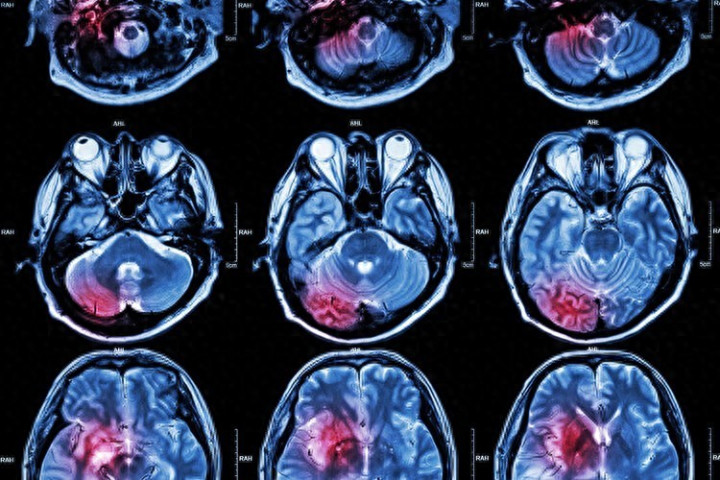

数据不是吓东说念主,是教导。多项议论与讲演指出:脑卒中始终位居中国住户主要死亡原因之列,疾病背负粗重。

而在中国,缺血性脑卒中(也便是全球常说的“脑梗”)占比额外高。

那问题来了:为什么中国脑梗越来越多?